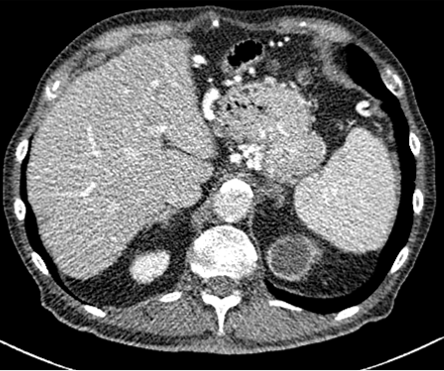

Figure 3: Comparison of existing methods and Ours. (a) LDCT, (b) N2C, (c) N2N, (d) N2V, (e) NDCT, (f) N2C+Ours, (g) N2N+Ours, (h) N2V+Ours.

Table. 1 shows the average PSNR and SSIM scores for supervised and self-supervised methods. Among the compared methods, N2C showed the highest LDCT denoising performance without the proposed techniques; with more significant improvements for all methods when the our methods were applied. Though N2N and N2V report higher scores than NDCT, with similar trends on natural image denoising, they were not very effective when applied to CT. We believe training by merely adding random noise (e.g., Gaussian), often very different from noise observed in CT is not useful for denoising, leading to poor results. Indeed, our method improved every learning method’s performance showing that the technique is model agnostic.

In Figures 2 and 3, we show comparison results of Pseudo-LDCT images and their generated noise using various methods, as well as the predictions of our method for each. In Fig. 2, Pseudo-LDCT images and their noise with Hist and Gaussian highlight a huge discrepancy between the actual LDCT image and its noise. In the case of random noise that is shown to be independently distributed across the entire image, it is often useful for natural image denoising. Moreover, this types of noise does not accurately reflect the nature of CT images. Through the proposed method, we show it is possible to generate Pseudo-CT images that preserve overall CT image characteristics with high quality (Fig. 3).